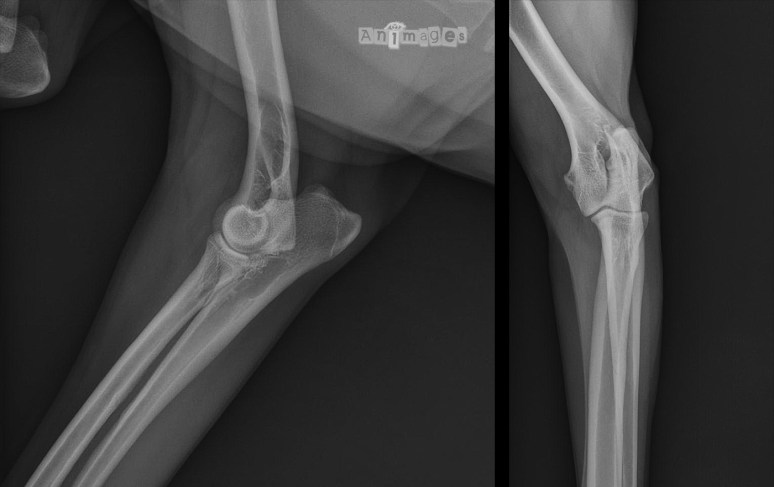

Signalement: Fugasse, Border collie stérilisée de 5 ans. Histoire clinique: Dimanche soir, Fugasse s’est sauvée dans les bois en courant après quelque chose. Elle est revenue le soir même, sans évidence de boiterie, mais il faisait bien noir et le proprio venait de terminer deux grosses Fin du Monde. Le lundi matin, Canelle s’est levée en traînant de la patte thoracique gauche, mais reste enjouée. Sa boiterie répond au deramaxx 25 mg lundi mais revient dès l’arrêt des antiinflammatoires. Fugasse aurait été opérée par son vétérinaire traitant au mois de mai au même membre pour y retirer plusieurs poils de porc épic incrustés.

Pas grand chose n’est-ce pas ? Comme la boiterie de Fugasse progressait sans répondre aux anti-inflammatoires, de nouvelles radiographies ont été prises 4 semaines plus tard…